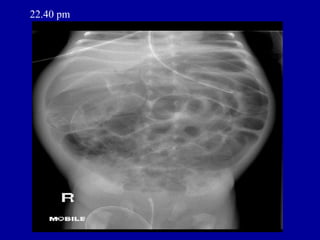

22.40 pm

ORIGINAL REPORT • HISTORY • Septicaemia. NEC. Intubated. • REPORT • MOBILE SUPINE (CHEST AND ABDOMEN) • The tip of the NG tube is projected over the distal esophagus. The tip of the ETT • is about 0.6cm from the carina. • A tube is projected over the rectal area. • There is diffuse haziness of both lungs. The heart size cannot be assessed. • There are multiple gas distended intestinal loops and intraperitoneal free gas present • which appears worse when compared to the last AXR.